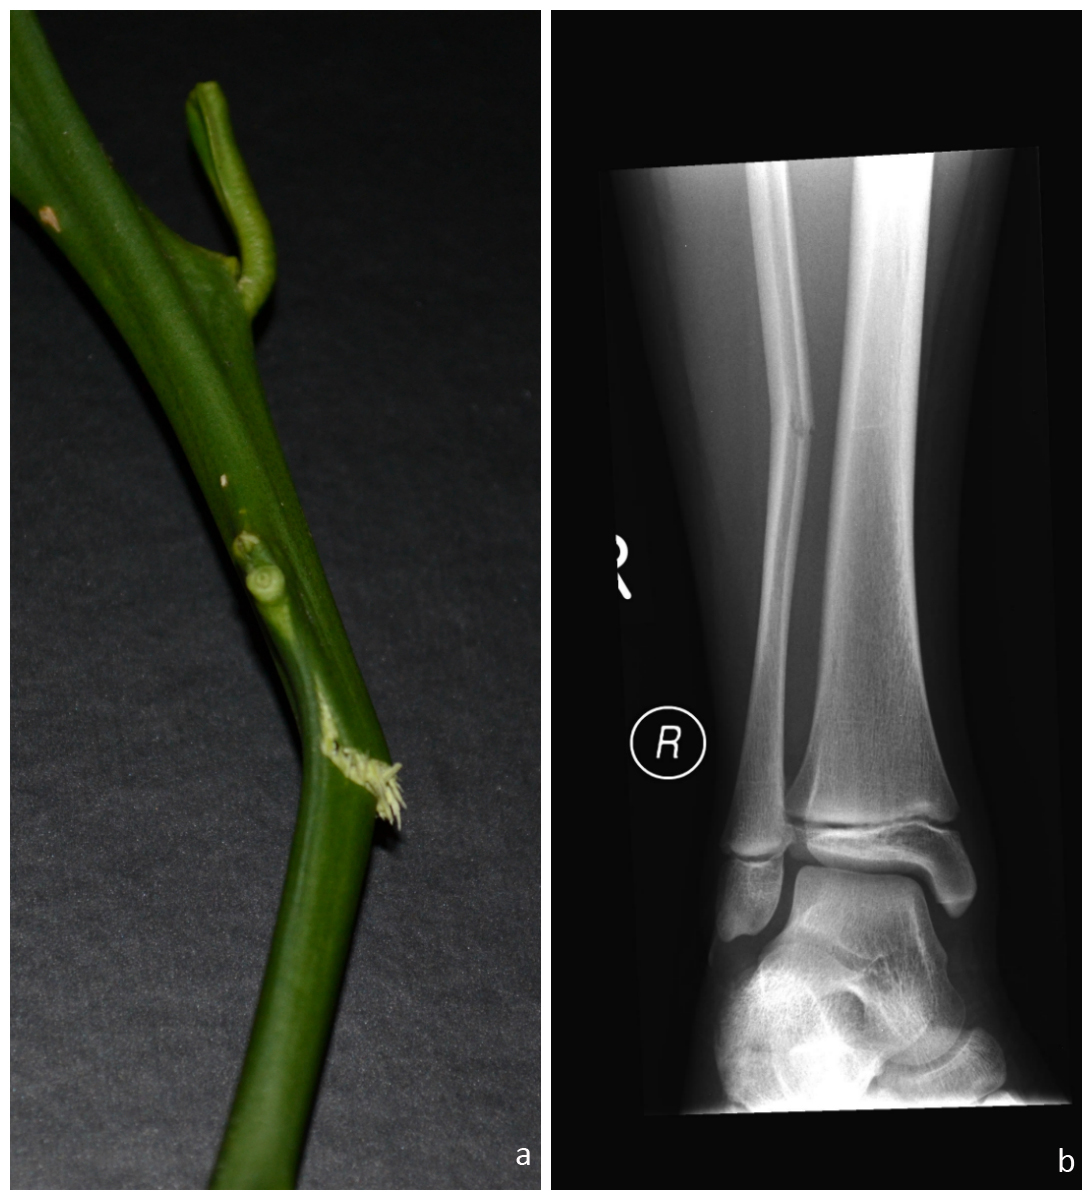

Fractura in lemn verde

A

la copii

incurbare incompleta a unei singure corticale

How well did you know this?